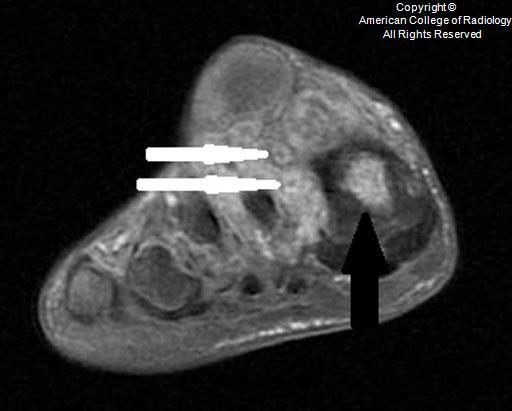

A

Medulla foot

• Medulla region in India

• also called mycetoma

• fungal (eumycetoma)

• bacterial (actinomycetoma)

• commonly seen in those who walk barefoot, such as agricultural workers

• patients typically present with painless swelling and a draining sinus tracts. The purulent discharge typically contains colored “grains” representing clumps of the causative organism

• Stage 0 – Soft-tissue swelling, which can become nodular and expansive.

Stage I – Extrinsic pressure on the bone causing bone displacement or scalloping. No bone involvement.

Stage II – Periosteal reaction or reactive sclerosis as a result of irritation of the bone surface by the causative organism.

Stage III – Bone erosion or cavitation as a result of penetration of the periosteum and cortex.

Stage IV – Joint involvement with longitudinal spread along a ray of metatarsal bone and phalanx.

Stage V – Horizontal spread limited to two rays of bone and confined to the hindfoot, midfoot, or forefoot.

Stage VI – Uncontrolled infection with multidirectional destruction

Dot-in-circle sign

• This sign refers to the characteristic high intensity spherical lesions on both T1- and T2-weighted images with a tiny central focus of hypointensity, resulting in the “dot in circle.”

• The high intensity spherical lesions are classically surrounded by a network of low intensity material.

• High intensity spherical lesions represent granulomatous inflammation, and the low intensity tissue surrounding the round lesions relate to a fibrous matrix.

• The tiny central focus of hypointensity correlates to the fungus ball or grains.